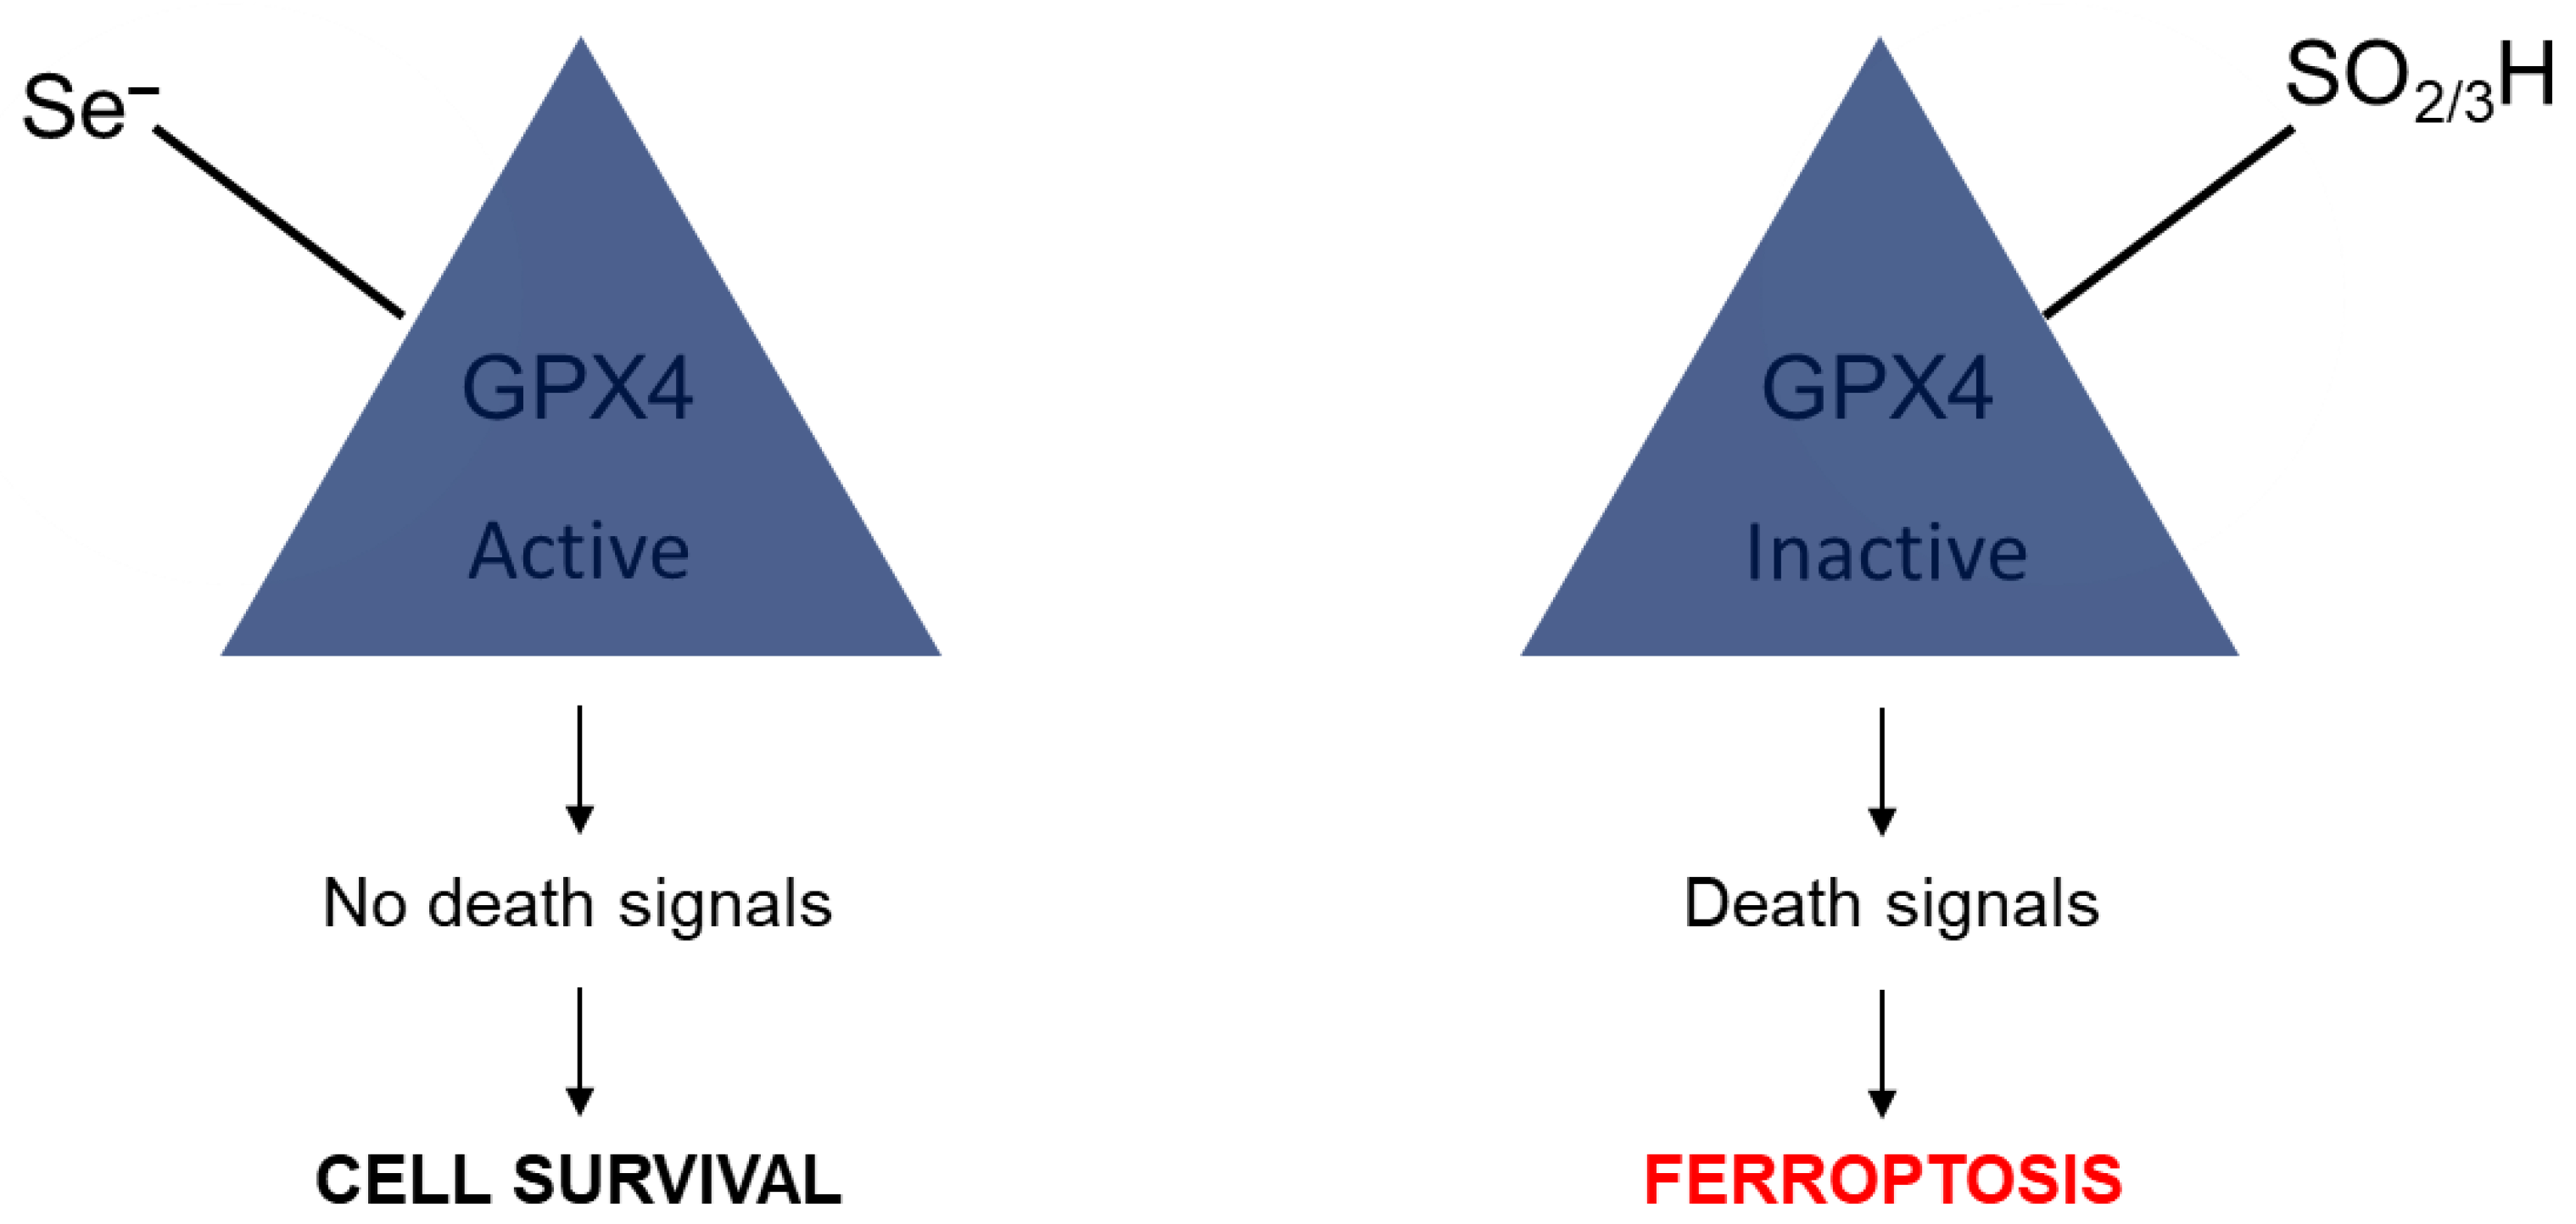

5. The Role of Selenium in Senescence and Ferroptosis